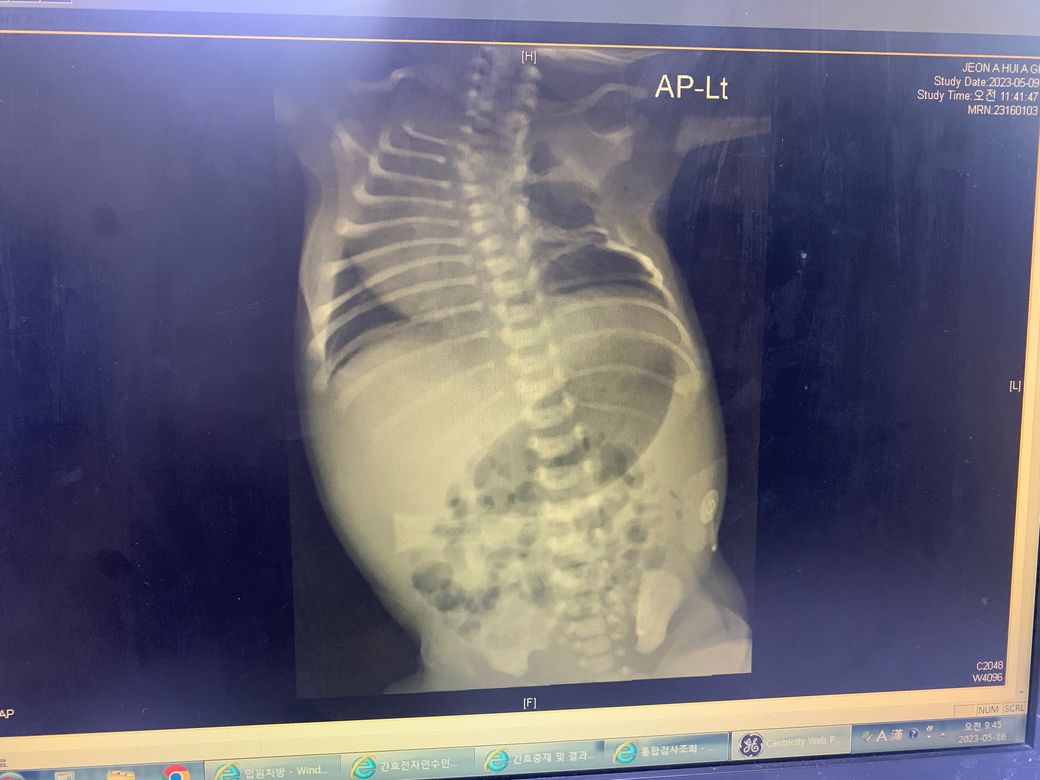

약 38주간 초음파,정밀초음파에서 갈비뼈가 정상이었는데

출산하고나서 엑스레이를 찍더니 갈비뼈가 없답니다...

초음파때 갈비뼈 개수까지 세었는데요.

지금 엑스레이는 정확하게 찍힌게 맞습니다. 왼쪽 위에 흉부쪽 갈비뼈가 문제가 있네요.

소아과에서 갈비뼈 형성부전에 대한 원인을 알아보셔야겠습니다.